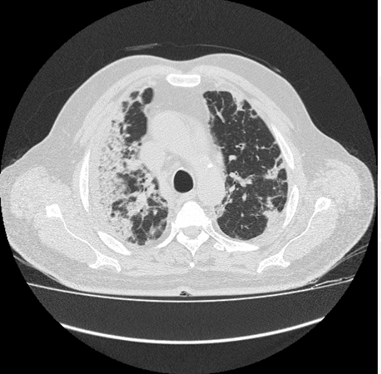

This image of the patient is with ground-glass opacities with the symptoms of milk short breath and fever. The figure 1 shows the day 1 imaging, in which the septal thickness is mild, as the symptoms grow to day 3, the thickness in found to be higher in the lungs of the patient, whereas a rise in ground-glass opacities is also observed.

Figure 1 Day 1 CT imaging.